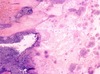

A

- bacterial endocarditis

- little irregular blue things = inflammatory cells

- bottom right corner = fibrin

- smudgy blue material = masses of bacteria

- bacterial endocarditis

- blue smudges = inflammatory cells or bacteria

- lighter pink = fibrin

- darker pink = collagen

* bacterial endocarditis

* smudgy groups = bacteria (in top left corner)

* more distinct dark purple = PMNs = below bacteria and in large clear cleft